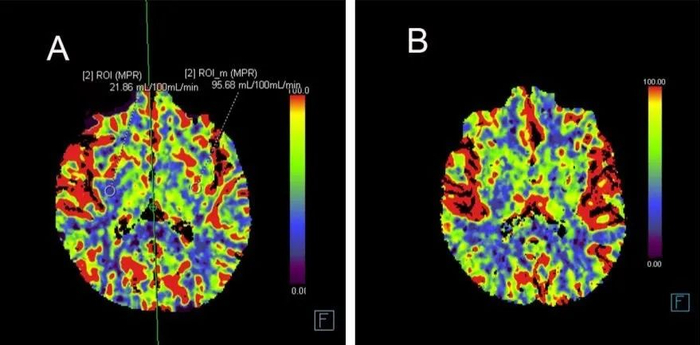

患者至西南医院神经内科就诊住院后左侧肢体麻木无力症状再次反复发作,经过缜密分析病史后,救治团队决定在发作期与发作间隙期分别进行头颅CTP检查,仔细读片后发现发作时右侧基底节区CBF较左侧下降(见图1)。为进一步明确患者脑血管病变情况,团队计划再行DSA脑血管造影并利用医院全球领先的7.0T核磁进行超高分辨率血管壁成像检查,经过仔细分析辨别讨论累计读片十余个小时后确定右侧大脑中动脉薄膜样增生突出管壁(见图2)。

图1. A发作期患者头颅灌注改变; B 发病间期患者头颅灌注表现